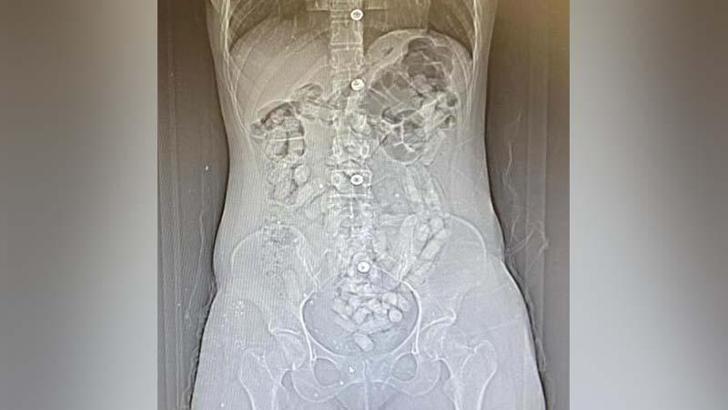

Savcılıktan alınan kararla götürüldükleri hastanede yapılan tomografi çekiminde, Khadıjeh S.'nin mide ve bağırsak bölümünde 31 parça halinde yaklaşık ağırlığı 252,52 gram ile Samıra T.'nin de 64 parça halinde 440,78 gram olmak üzere toplam 95 parça halinde 693,3 gram Afyon sakızı ele geçirildi. Gözaltına alınan şüpheliler, emniyetteki sorgularının ardından 'Uyuşturucu madde ticareti yapmak' suçundan adliyeye sevk edildi. Allahnıaz S. adli kontrol şartıyla serbest kalırken; Khadıjeh S., Samıra T. ve Raheleh Y. tutuklandı.